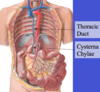

Label all:

Label: